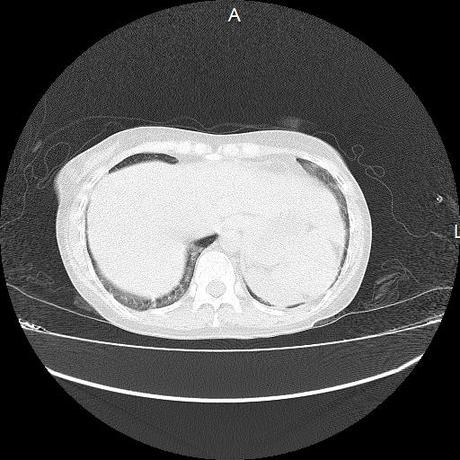

Ambos hemidiafragmas sin evidencia de alteraciones.

En los cortes valorados de abdomen hígado, bazo y páncreas sin evidencia de alteraciones, glándula suprarrenal izquierda con imagen ovalada, bordes definidos, homogénea, mide 11 mm en probable relacion a adenoma.

- PROBABLE ADENOMA DE SUPRARRENAL IZQUIERDA.